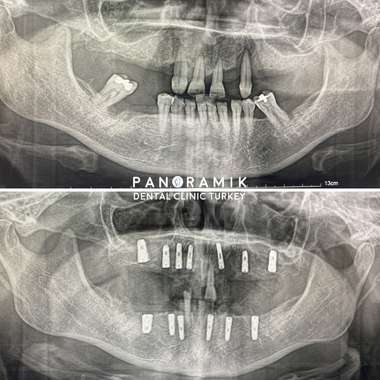

Full Mouth Implants

The condition of having no teeth in the mouth is called complete edentulism. There are multiple treatment options for our patients who have no teeth. Implant treatment is one of these methods.

What Is Implant in Complete Edentulism?

Implant in complete edentulism is the absence of any tooth in the mouth and the application of implant treatment in this case. After tooth loss, bone loss and related aesthetic, health and functional problems arise. In patients who have lost all their teeth for various reasons, 2 to 4 implants can be placed. Removable prostheses are prepared on these implants. The aim is to prevent the tooth from moving while talking, eating and even sneezing with implant supports. After the removable prosthesis option in implant treatment in total edentulism, the other option is fixed prosthesis. In this option, the prosthesis is glued onto the implant and a natural tooth appearance is obtained.